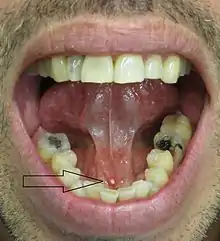

![]() حصى لعابية أُزيلت من الغذّة تحت اللسان حصى لعابية أُزيلت من الغذّة تحت اللسان | |

عادةً ما يكون التشخيص لهذا المرض بسيط وواضح، أحيانا بإمكان الطبيب أن يرى أو يلمس الحصوة من خلال فتحة القناة أسفل اللسان .

وكذلك الأشعة التشخيصية أو الأشعة سينية الخاصة بالغدد اللعابية (حقن مادة مشعة تبين مكان وحجم الحصوة التي يتراوح قطرها ما بين 2 سم إلى 10سم) تساعد كثيراً في التشخيص للتفريق بين الحصوة أو اي سبب آخر للورم الذي من الممكن ان يتكون في هذه المنطقة.